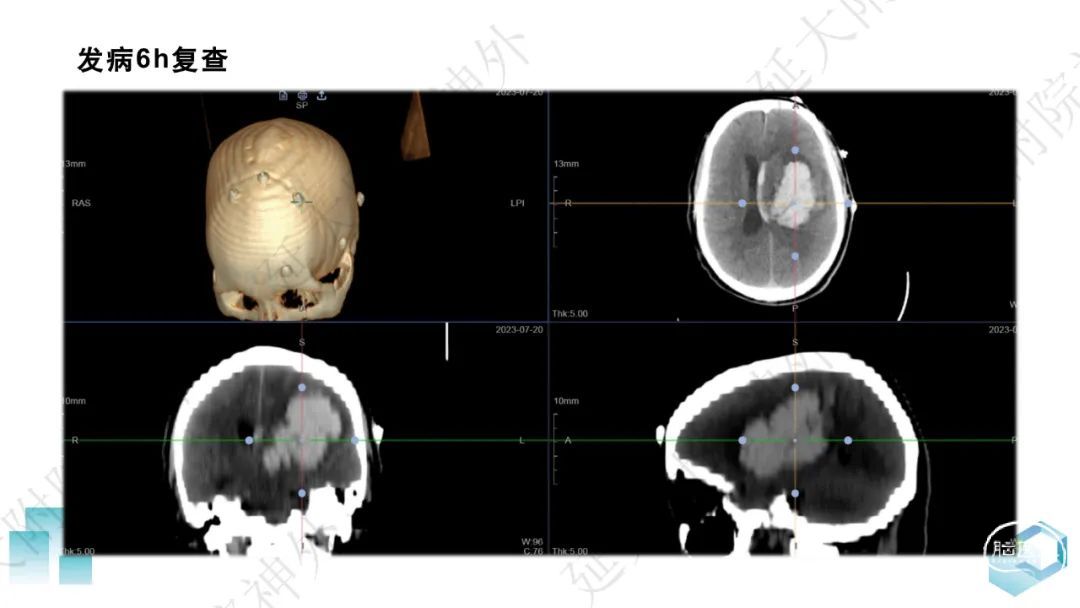

今天为大家分享的是《监测有道丨颅脑创伤-神经重症周刊》第332期,由延安大学附属医院神经外科贾云峰主任医师带来的:左侧基底节区出血破入脑室一例神经内镜下血肿清除术,欢迎阅读、分享。